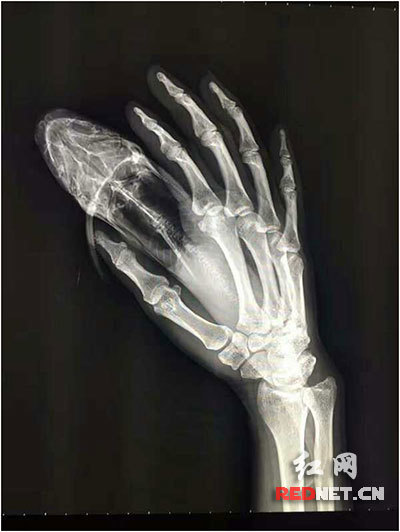

X光片中,可明显看到黄芬手上鱼刺的位置

“拍了X光片,幸好鱼刺没有被患者拔断。”长沙市第三医院骨科医师刘文前介绍,“‘黄鸭叫’背上鱼鳍的刺是锯齿状的,如果患者强行拔出鱼刺很有可能造成鱼骨断裂在伤口内,伤口会很大,甚至会感染。”刘文前先用咬骨钳把留在体外的鱼刺剪断,将鱼身和鱼鳍分开,然后在局麻状态下帮患者取出体内的鱼刺。“手术过程很顺利。”术后,刘文前给患者实施了抗炎治疗,并注射了破伤针。